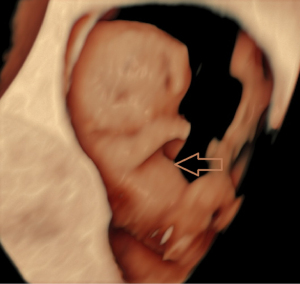

Chief complaint: a 27-year-old gravida presented for routine prenatal ultrasonographic evaluation. Early first-trimester ultrasound surveillance (6 weeks) revealed unremarkable fetal development. The patient denied any pregnancy-associated discomfort at this stage. History: bilateral salpingectomy performed. Personal and family history: the patient had no significant family or genetic history. Physical examination revealed no remarkable findings. All laboratory parameters fell within established normal limits. The patient used ART due to tubal factors. On 16 June 2024, the patient underwent a frozen-thawed blastocyst transfer. The two-dimensional (2D) ultrasound examination at 6 weeks of pregnancy showed a gestational sac in the uterine cavity, with a yolk sac inside and a 0.52 cm-long fetal bud close to the yolk sac, which showed a faint primitive heart tube pulsation. Ultrasound examination at 8 weeks of pregnancy showed a gestational sac in the uterine cavity, with one yolk sac, an amniotic sac, and two fetuses in the gestational sac. One fetus had a crown-rump length of 2.03 cm, and the other fetus had a crown-rump length of 1.88 cm. Both fetuses were consistent with an 8-week pregnancy. Both fetuses demonstrated complete thoracic ectopia cordis with anterior protrusion and cardiac fusion. The sagittal section showed that the two fetuses had a “ball-holding” sign, with a common heartbeat of 169 bpm (Figure 1). The organs above the umbilical part of the two fetuses were connected and protruded towards the front of the abdomen, with a cover on the surface. The cross-section of the chest showed that the two fetuses showed a “dumbbell” sign (Figure 2). The umbilical cords of the two fetuses were fused into a thick umbilical cord, and the entrance end of the umbilical cord abdominal wall was inserted into the fusion of the umbilical cord. The distal end of the umbilical cord was bifurcated and inserted into the placental parenchyma, respectively. Three-dimensional (3D) ultrasound surface imaging intuitively showed the relative positional relationship between the two fetuses and the exposure of the conjoined twins to the heart that fused each other on the outside of the chest cavity (Figure 3). Due to the early gestational week, the anterior diaphragmatic midline of the two fetuses was unclear. The ultrasound machine used in this case was a GE Voluson E10 (GE Healthcare, Chicago, IL, USA), with a RIC5-9-D probe. Figures 4,5 show normal fetus control images at the same gestational age.

With the widespread application of high-resolution transvaginal ultrasound, visualization of early pregnancy has become possible. The accuracy of assessing the risk of fetal chromosomal abnormalities through early pregnancy ultrasound combined with biochemical markers has improved, leading to the diagnosis of more fetal abnormalities in the early stages of pregnancy. A study indicated that ultrasound diagnosis of conjoined twins typically occurs between 11 and 13 weeks and 6 days. Screening at this stage can detect the most severe fetal malformations (8). There are reports that high-resolution ultrasound has advanced the diagnosis of conjoined twins to 7 weeks of gestation. However, due to the early gestational age, it is difficult to precisely determine the specific type of connection between the twins, and color Doppler ultrasound is typically required to assist in diagnosing the presence of conjoined twins (9). Fetal development is a process, and it can only be detected by ultrasound once it has reached a distinguishable gestational age. When fetal activity increases, around 8 weeks of gestation, it becomes easier to distinguish between monochorionic twins and conjoined twins (10). The patient underwent an ultrasound examination at 6 weeks of gestation, during which only a small, short, line-like embryonic bud and weak fetal heartbeat were observed. During the ultrasound examination at 8 weeks of gestation, we discovered that the two fetuses were embracing a “spherical” structure. The sagittal section revealed the “ball-holding” sign, and the transverse section showed a notch at the junction of the thoracic and abdominal walls, presenting the “dumbbell” sign. These two signs are specific to thoracoabdominal conjoined twins, with both fetuses affected by Cantrell’s pentalogy. Transvaginal 2D and 3D ultrasound provides direct evidence for the early identification of a special type of conjoined twins and advances the diagnostic gestational age to 8 weeks. Through transvaginal 2D ultrasound, the issue was identified, followed by adjusting the probe direction and angle to locate the specific connection site of the conjoined twins and determine the type of connection. The multiplanar views of 3D ultrasound provide additional detailed information. Adjusting the direction of light incidence, rotating the probe at multiple angles, and adjusting the 3D image, combined with surface imaging mode, yields more detailed features. The combination of 2D and 3D ultrasound provides more information than 2D ultrasound alone, offering more intuitive images, particularly suitable for fetuses with abnormal external features. A study has confirmed the role of 3D ultrasound in diagnosing prenatal abnormalities, which is consistent with our findings (11).

In summary, conjoined twins with bilateral Cantrell’s pentalogy likely represent the most severe phenotypic manifestation with the poorest prognosis. The characteristic “ball-holding” and “dumbbell” signs on ultrasonography serve as pathognomonic indicators of this condition in monochorionic monoamniotic twins. Early recognition of these sonographic markers is critical for timely diagnosis and management.